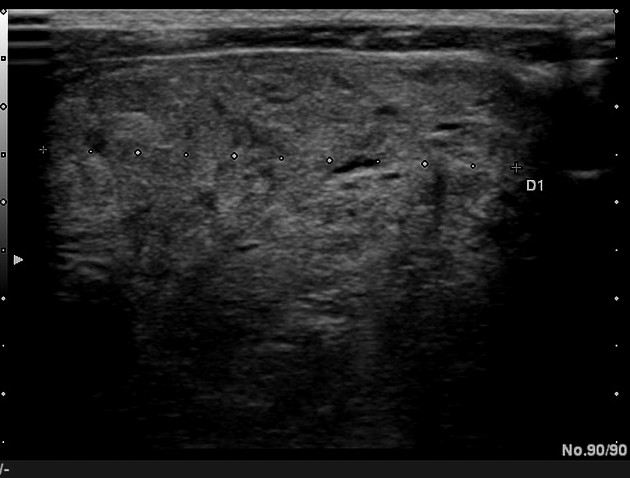

what thyroid pathology is shown here?

simple thyroid cyst